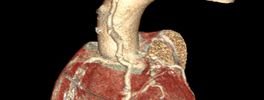

CT Heart

CT Cardiac Anatomy